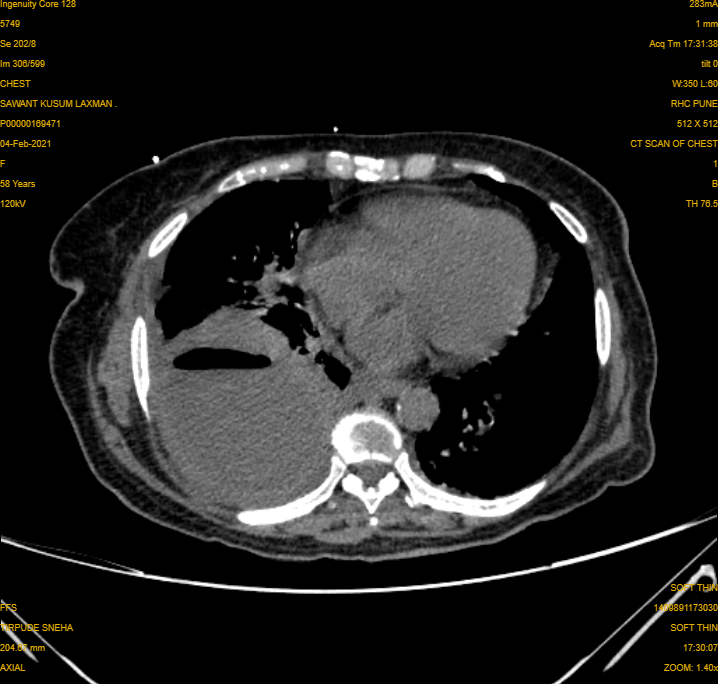

| CT scan with contrast helped us delineate that it was the Lung covering filled with Pus |

Pus anywhere in the body almost always needs to be drained. Diagnosis: We call this condition as Empyema Otherwise it leads to Spread of infection locally and in blood, which can be fatal. The reason for her pus collection seems to be uncontrolled undiagnosed diabetes. Yes this is a hazard of Diabetes, a new infection.